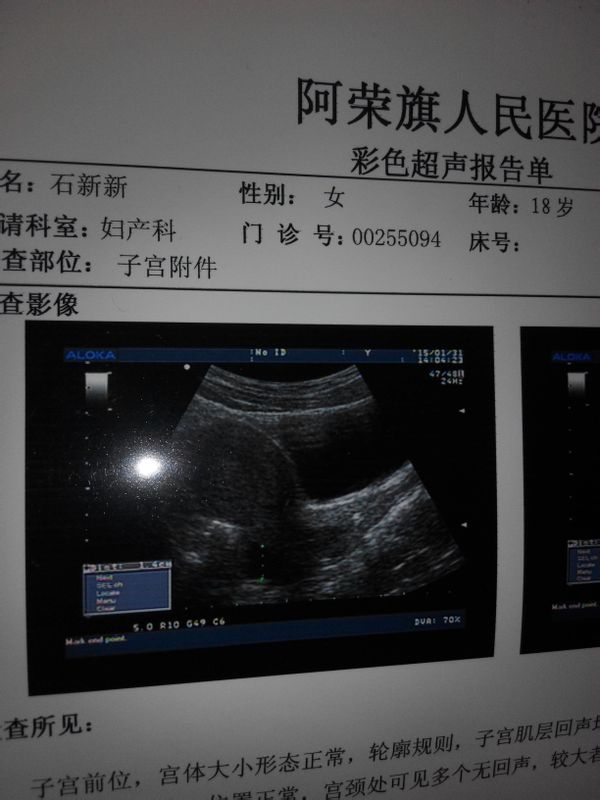

子宫前卫,宫体大小形态正常,轮廓规则,子宫肌层回声均匀,内膜厚约1.2cm,宫腔内可见节育器回声

位置正常,宫颈处可见多个无回声,较大者cm×cm,边界清晰,CDFI未见异常流血信号,双侧卵巢大小正常,内部结构清晰,双侧附件区未见明显异常回声,子宫直肠窝可见少量液性暗区,深约1.4cm。不太明白这些是什么意思,请大家帮忙解答,心里总有疑惑,是不是宫外孕啊